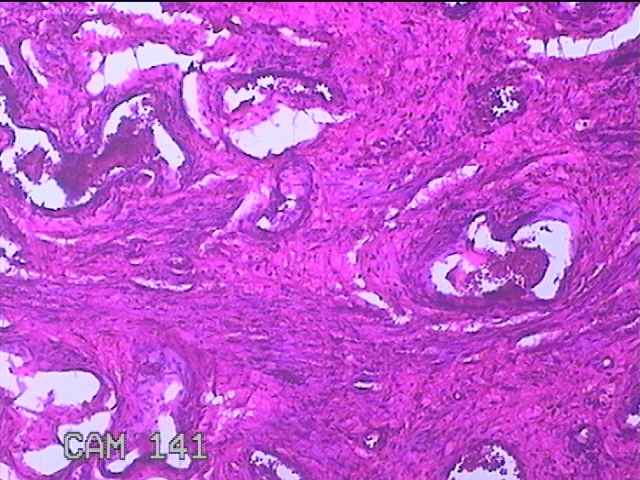

阴道后壁组织

性别

女

年龄

44岁

临床诊断

阴道前后壁膨出Ⅱ度

一般病史

分娩厚19年,阴道肿物膨出2月,加重3周。

标本名称

大体所见

灰白粉红色组织4.5x2.8x0.7cm一块,表面糜烂,切面灰白粉红色,质软。